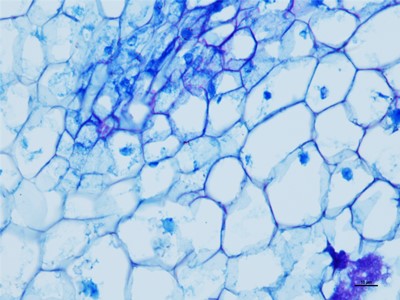

我们要在显微镜底下观察细胞的时候,就得把组织和细胞以及需要观察的东西切片,这些就得控制在厚度大概在1-10微米,这个厚度是最好观察物质的,如果没有在这个厚度之间的切片基本在观察就没有什么颜色。下面陕西依科生物技术有限公司针为大家介绍HE染色的具体操作步骤。

HE染色是基本病理的染色技术,HE染色是病理医生可以正确判断的唯一准则,首先在做实验的时候要准备乙醇、冰丙酮、苏木精染液、伊红染液、二甲苯、新疆中性树胶、培养瓶、培养皿、盖玻片、载玻片、显微镜等一些器材。首先将新疆石蜡切片脱蜡然后在将切片放进二甲苯无水乙醇,酒精,然后切片在放进伊红染色液中染色,然后就是将切片放入酒精和无水乙醇、二苯甲,脱水然后将切片拿出晾干,然后在封片。然后在用显微镜观察,图像采集。我们在做HE染色的实验时要注意以下细节,首先是脱蜡时要保持干净,已经苏木精染色的时间。以上就是HE染色的操作流程。